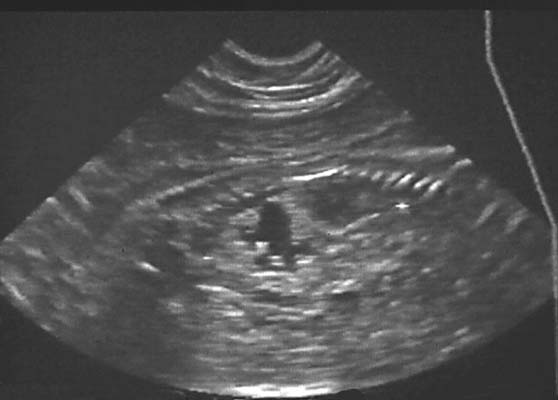

Anéchogène ovalaire